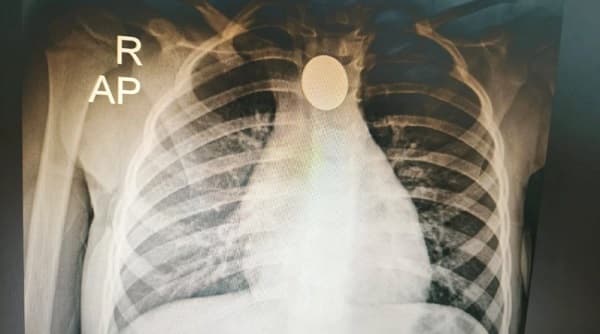

Una radiografía de tórax reveló la presencia de un objeto metálico en el bronquio izquierdo. Ante este hallazgo, el paciente fue derivado al Ineram, donde se confirmó que se trataba de cinco piezas dentales alojadas en su pulmón, lo que explicaba las dificultades respiratorias persistentes.

El equipo médico liderado por el doctor Carlos Morínigo llevó a cabo la cirugía para extraer los dientes. Según el reporte posterior, el procedimiento se realizó con éxito y el paciente se encuentra en etapa de recuperación, bajo seguimiento especializado para descartar complicaciones posteriores.